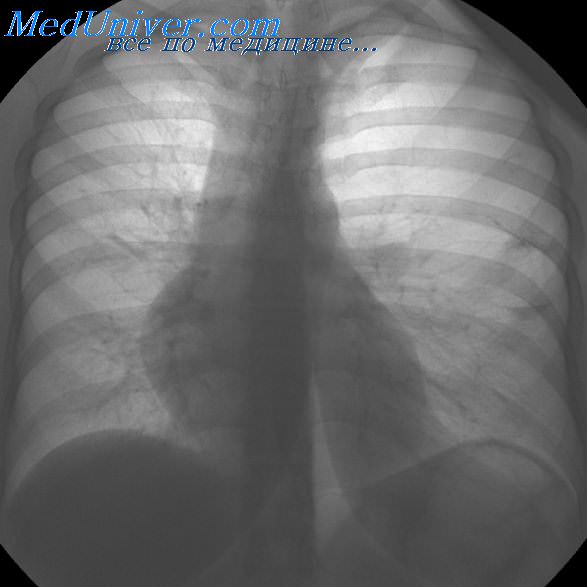

Рентгеновские снимки при врожденной эмфиземе легкого

Раздел: Визуальные уроки